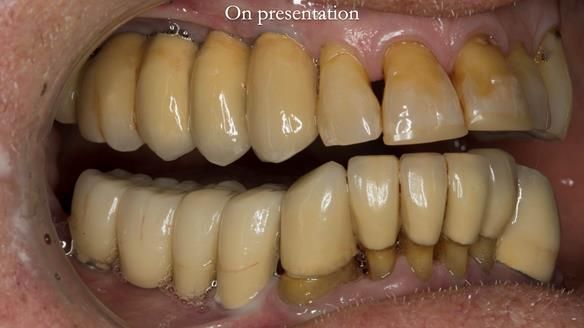

Final thoughts

This case was always about function, not aesthetics.

Ken’s teeth were never going to look perfect.

There were stained composites, old restorations, and obvious wear.

That was accepted from the outset.

What matters is that the dentures worked.

The way Rowan lengthened the teeth — particularly in the upper RPD — to match the existing gingival recession on the remaining teeth was superb. The dentures sit naturally within the context of the rest of the mouth.

Most importantly, Ken could eat comfortably, speak normally, and get on with his life without thinking about his teeth. There were no ongoing problems. No drama. No repeated interventions.